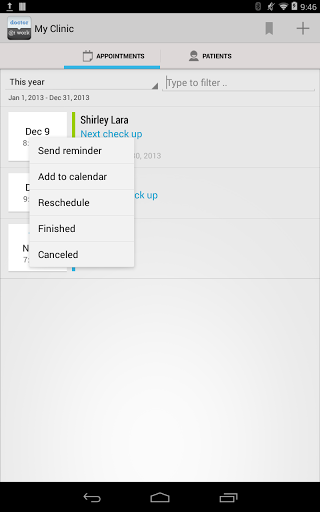

• Envoyer un rappel de rendez-vous médical au patient par courriel ou par SMS

• Exporter un rendez-vous vers le calendrier android